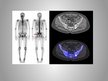

Radioizotopiskā diagnostika

Radioizotopās diagnostikas metodes

Staru terapijas metode – radioterapija

Staru terapijas metode - radioterapija

Jonizējošā starojuma ietekmē organisma audi noārdās (slimie audi ir neizturīgāki);

Lokāla ārstēšanas metode;

Ārstē audzējus un dažādus iekaisumprocesus.

Cik jutīgi ir audzēji pret apstarošanu?

• ļoti jutīgie (limfomas, Vilmsa audzējs nierēs, seminoma);

• vidēji jutīgie (plakanšūnu vēži, krūts vēzis);

• rezistentie jeb praktiski nejutīgie (sarkomas, melanomas, gremošanas orgānu adenokarcinomas).

Process

Bieži izmanto kobaltu-60;

No svina konteinera γ stari izplūst uz notēmēto vietu;

Avots rotē ap pacienta ķermeni, lai samazinātos veselo šūnu bojājumi.